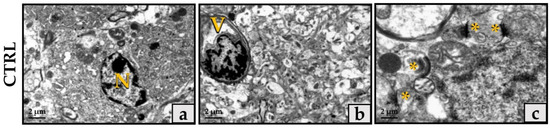

3.2. Ultrastructural Hippocampal Evaluation of the Sedentary and Trained Mice